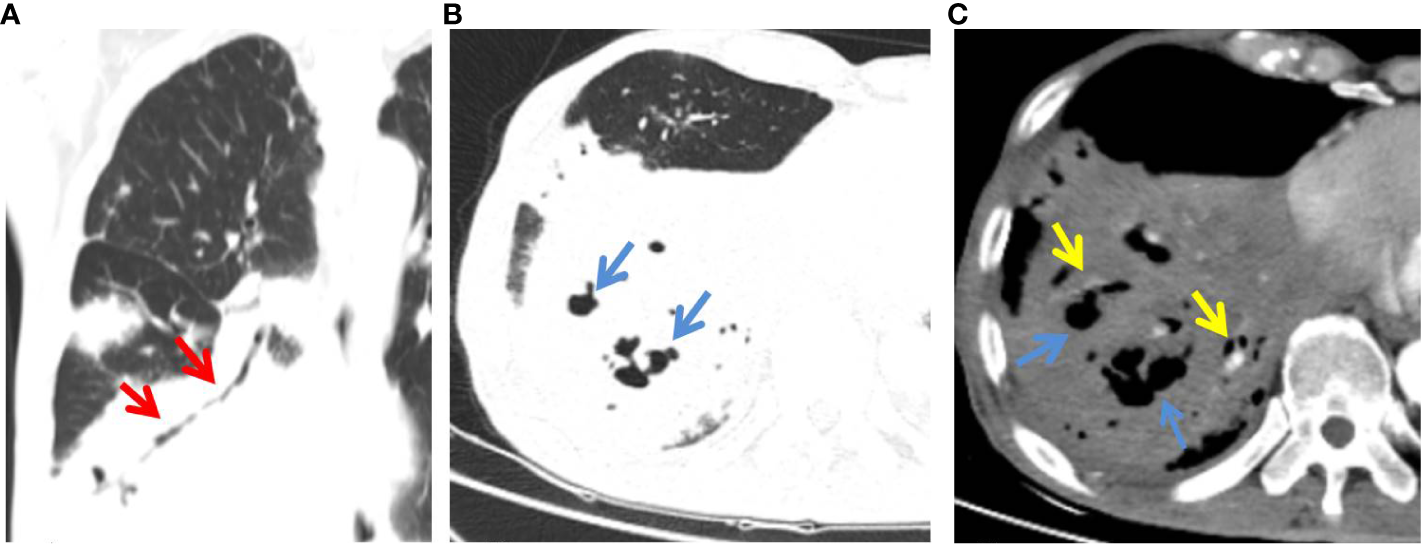

Figure 2

C-MALT lymphoma in a 58-year-old woman with right back pain for 2 weeks. (A) Lung-window HRCT multi-planar reconstruction showed a consolidation with air bronchogram (red arrow) in the right lower lobe. (B) There was cystic bronchiectasis (blue arrow) within the lesion. (C)Â Mediastinum-window showed consolidation with cystic bronchiectasis (blue arrow) and angiogram sign (yellow arrow). HRCT, high-resolution computed tomography; C-MALT, consolidation pattern of pulmonary mucosa-associated lymphoid tissue.